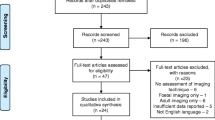

The stated search strategy initially yielded 5268 records from SCOPUS and MEDLINE databases. No records were retrieved from the OpenGrey database. A further 395 records were identified after a repeat search in May 2021. After removing duplicate entries, screening of abstracts and titles and screening the full text of 66 papers, an additional 6 records were identified based on citations and references. Including these 6 papers, a total of 22 papers fitted our inclusion criteria, limited to the application of MRI to natural (endogenous) brain tissue pulsations. A modified version of the PRISMA flowchart, summarising the processes for systematic identification of eligible papers, is provided in Fig. 1 [14].

Modified PRISMA flowchart summarising the systematic search process [14]